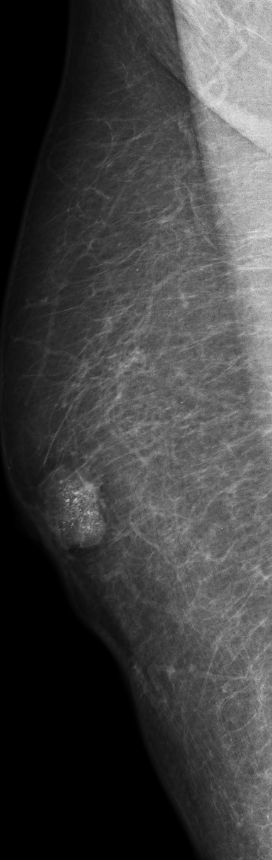

| DCIS | 80-jähriger Mann mit einem Knoten rechts retromamillär. Mammographie: Dichter Knoten mit multiplen Mikroverkalkungen unmittelbar periareolär. Histologie: papilläres DCIS, G2, 19 mm, ER: 12/12, PR: 6/12, Ki-67: 20%. Th.: Exzision, Radiatio der Mamma, TAM über 5 Jahre | ||||

rechts MLO![]() |